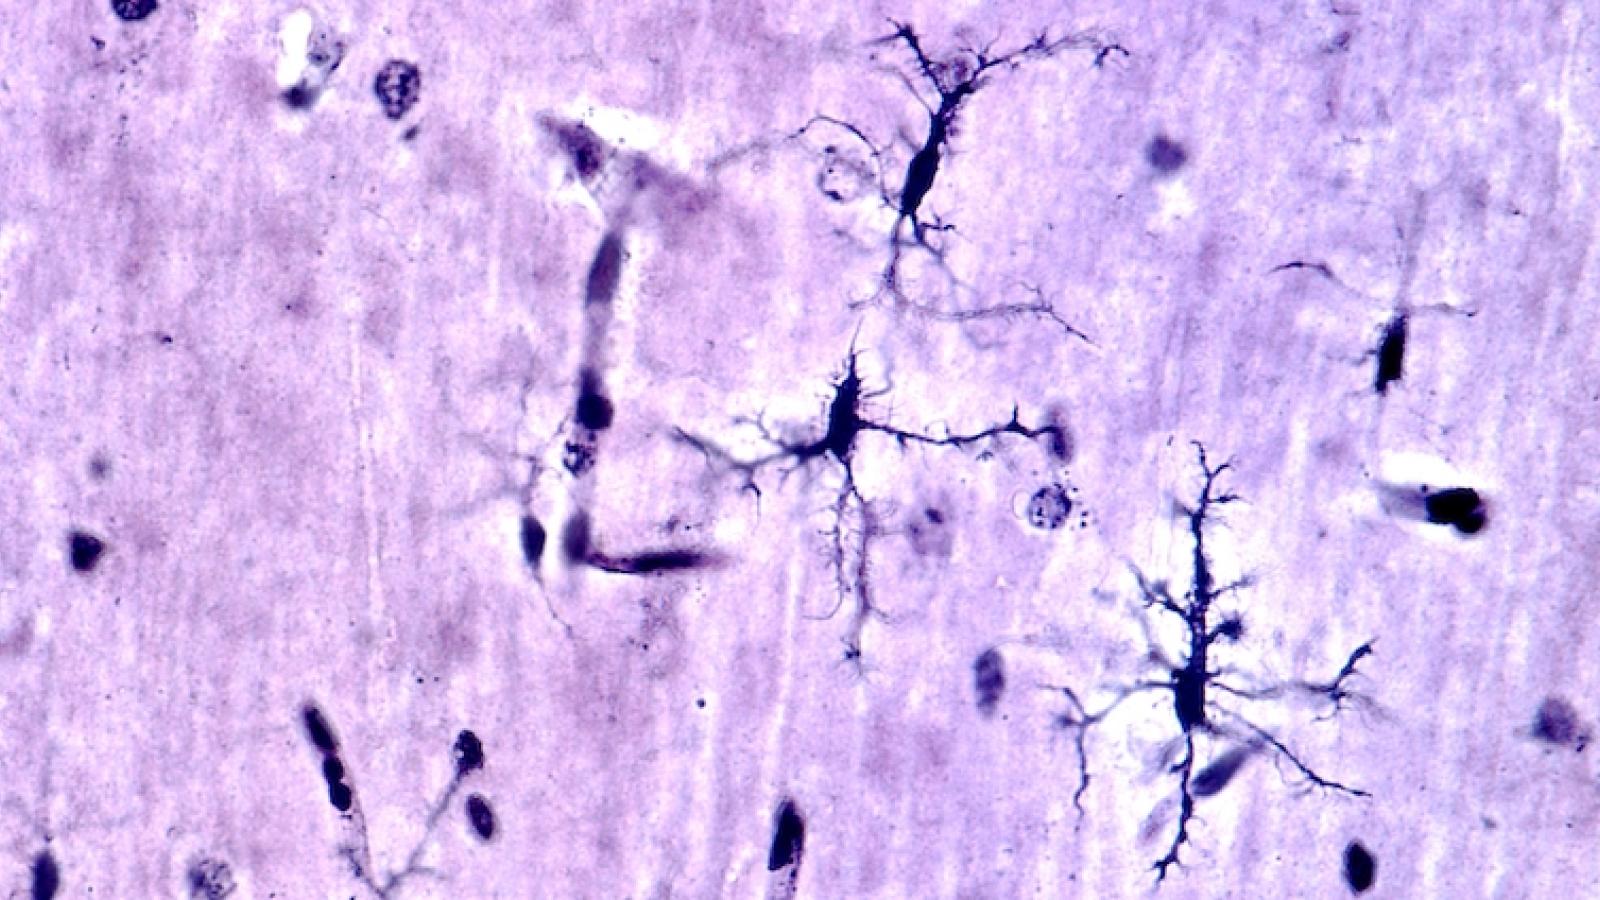

Neuroimmune mechanisms of neuronal imbalance in Alzheimer's disease

Microglia, the brain’s primary immune cells, are implicated in Alzheimer’s disease, but the reasons behind this are not well understood. Synapses, the connection points between two neurons, are lost in Alzheimer’s and this correlates to memory impairments. People with Alzheimer’s also show elevated electrical brain activity. This project, in collaboration between the UK DRI at UCL and Imperial, will investigate whether there is a link between these three aspects: increased electrical activity, synapse loss and microglia, in order to increase fundamental understanding of the role of microglia in Alzheimer’s disease.

Banner image: Shutterstock / Jose Luis Calvo